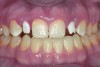

Fig 1. Preoperative view of implants (Biomet 3i) with encode abutments.

Figure 1

An example of the process using the True Definition Scanner to digitally record the position of a Biomet3i (Biomet, Inc., www.biomet.com) implant using an Encode® (Biomet) abutment can be seen in Figure 1 through Figure 6. The Encode healing abutment is placed on the implant to extend at least 1 mm supragingivally to make its geometry available for intraoral scanning (Figure 1). The True Definition Scanner records the intraoral data (Figure 2), and the digital file is transmitted electronically to the Biomet 3i Design Lab for design (Figure 3) and fabrication of the desired custom abutment. Once the design file is approved by the laboratory, the abutment is inserted into the digital file, and an SLA model (Figure 4) can be processed for fabrication of the final restoration (Figure 5 and Figure 6).